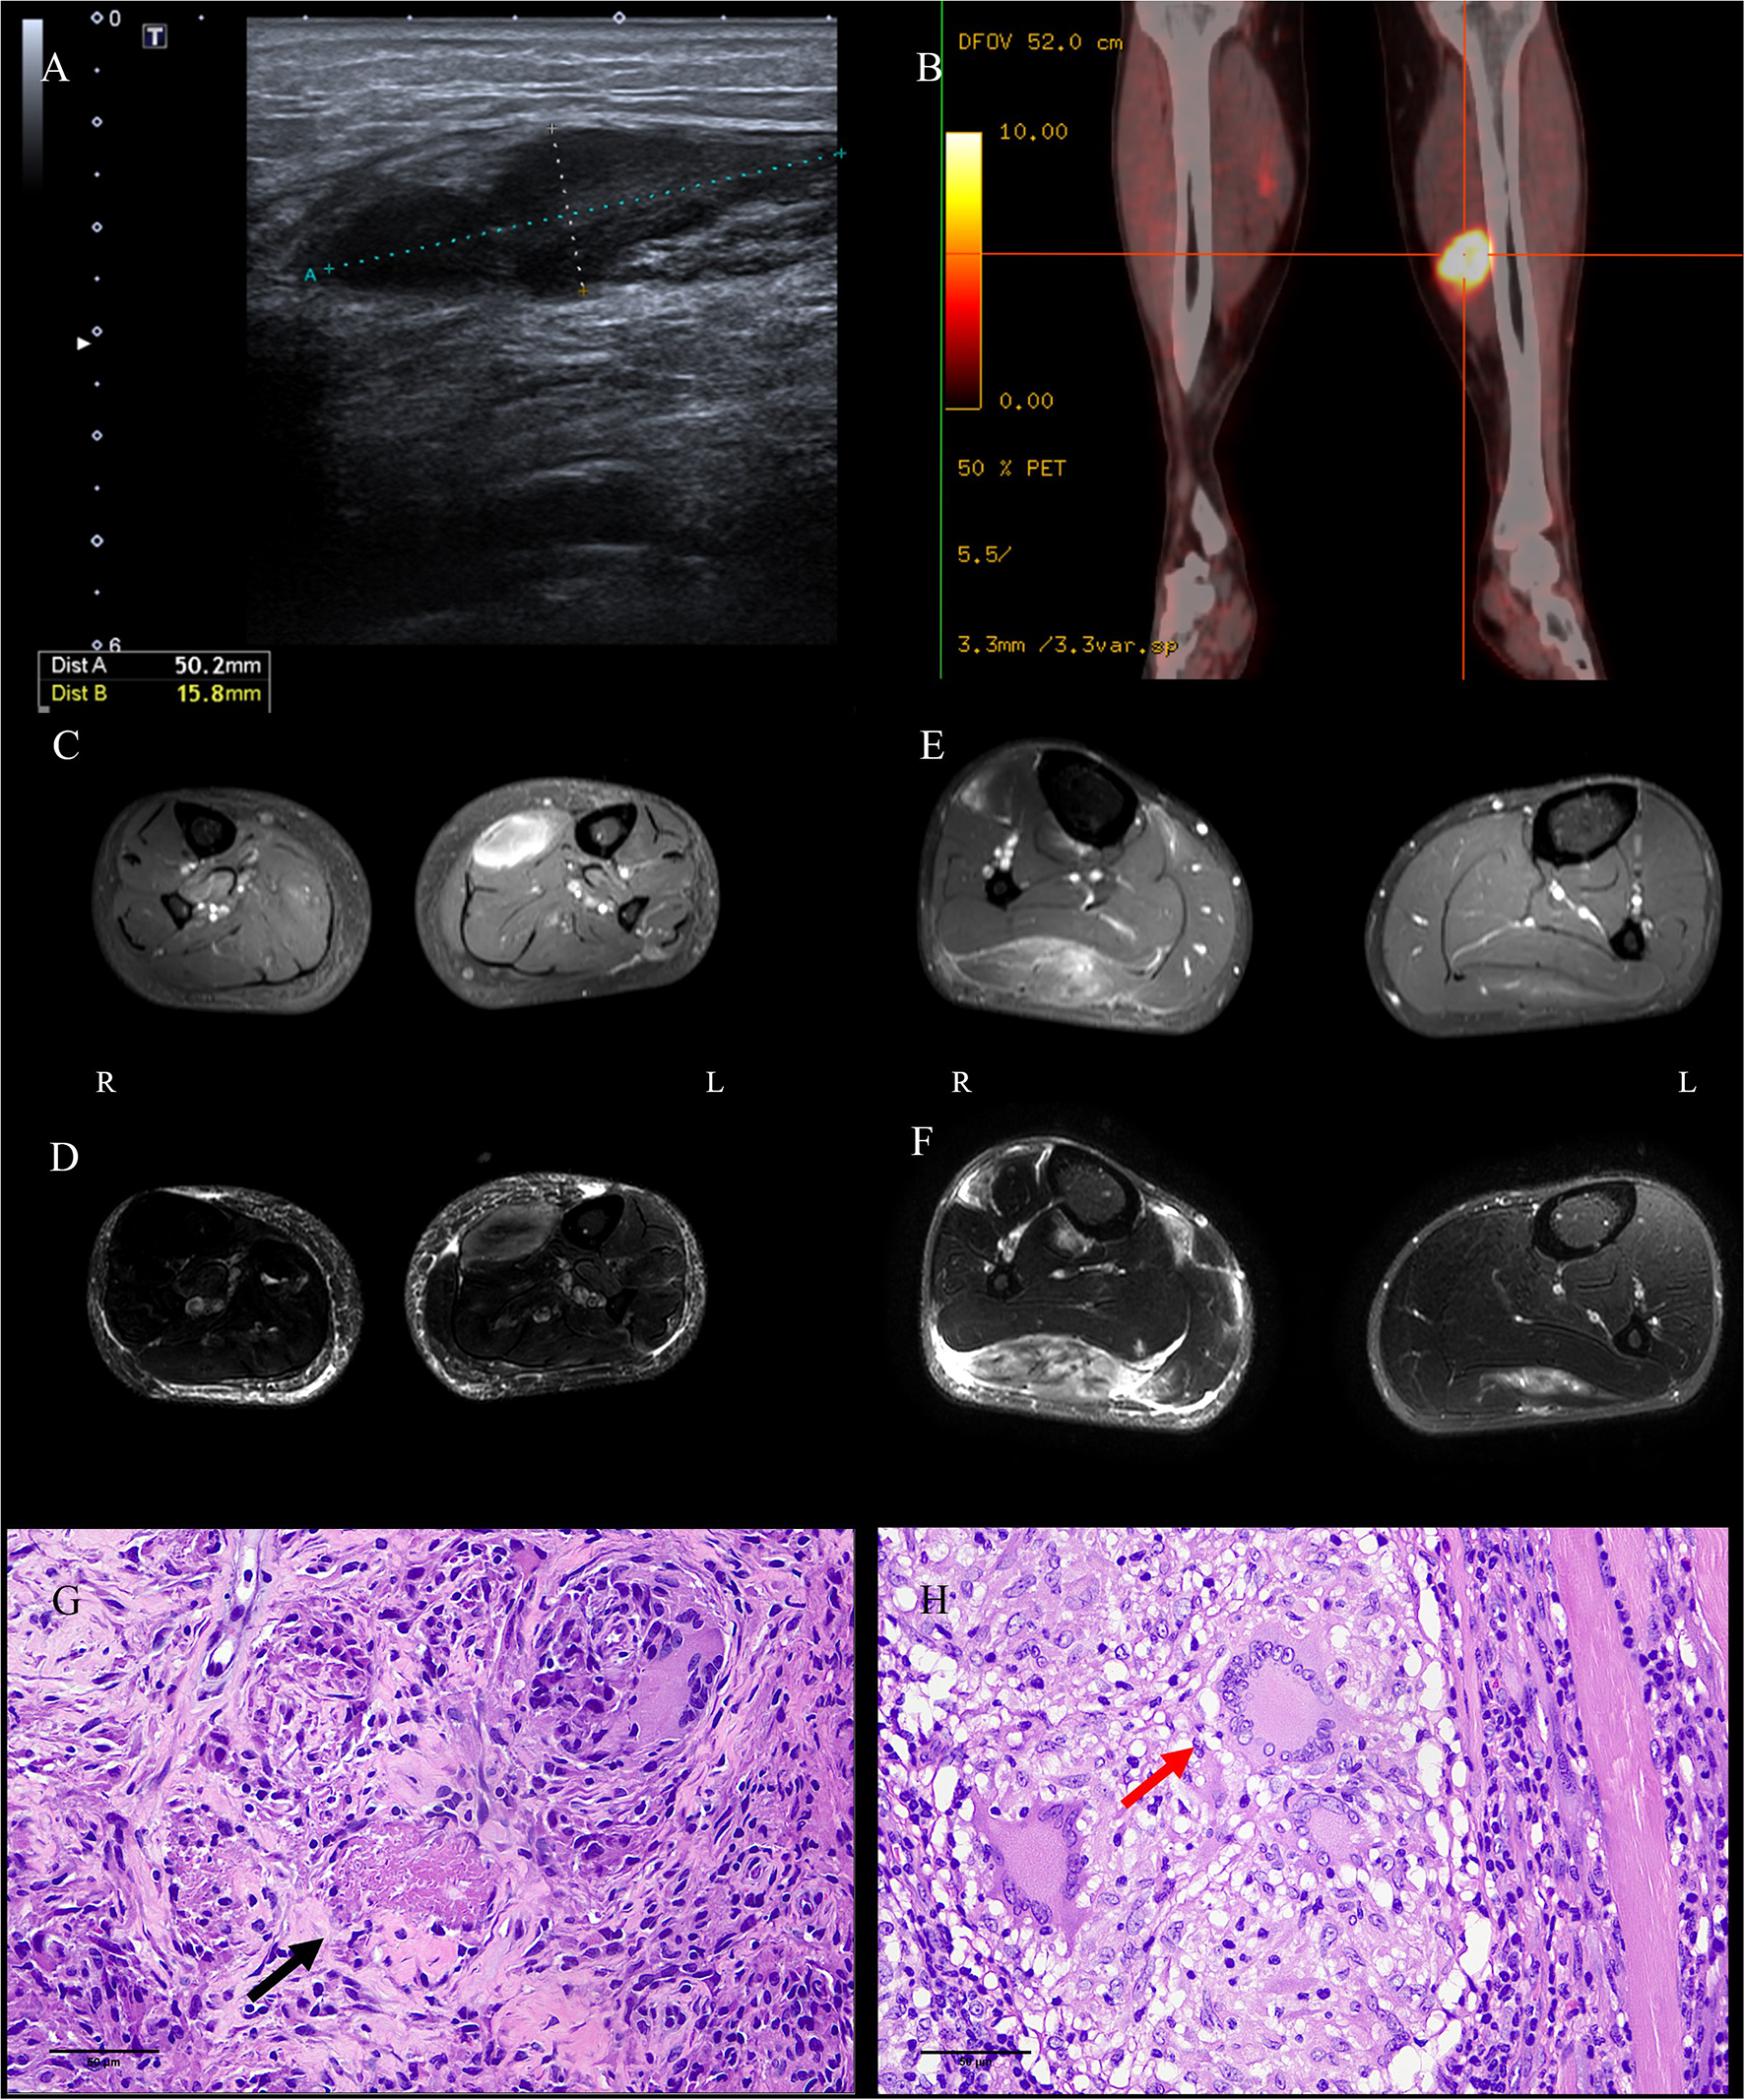

Chest computed tomography (CT) of case 1 revealed scattered bilateral inflammatory changes in the inferior lobes of both lungs and multiple nodular thickening on both sides of the pleura. Bilateral ultrasound of the calves suggested a 50 × 16-mm hypoechoic lesion in the left soleus muscle (Figure 1A) and a 43 × 6-mm hypoechoic lesion in the medial head of the gastrocnemius muscle. Additionally, 18 F-fluorodeoxyglucose positron emission tomography–computed tomography (18 F-FDG-PETCT) revealed multiple hypermetabolic lesions, which involved the left soleus muscle, the left musculus fibularis longus, the right soleus muscle, and the tibialis anterior muscle. The largest lesion was located on the middle of the left soleus muscle measuring 33.8 × 20 × 42 mm, and the maximum standardized uptake value (SUVmax) was 15.9 (Figure 1B). Magnetic resonance imaging (MRI) examination showed abnormal mass signals involving the inner front edge of the gastrocnemius muscle. The lesion was enhanced by gadolinium on the T1-weighted turbo spin-echo (T1W-TSE) image, and T2-weighted spectral presaturation attenuated inversion recovery (T2W-SPAIR) showed a hyperintense mass. There was a similar lesion in the gastrocnemius muscle of the right leg (Figures 1C, D). Pelvis and lumbar spine MRI showed mild lumbar disk herniation, with no other abnormal findings.

Figure 1

Images and pathological findings of the muscle masses. The lesion in the left soleus muscle of P1 was found to be hypoechoic on ultrasound (A), hypermetabolic on PETCT (B), enhanced on axial enhanced T1WI-TES (C), and light-hyperintense on T2W-SPAIR (D). Several well-formed epithelioid granulomas centered by caseous necrosis were observed [(G), HE, bar = 50 μm]. The lesion in the right gastrocnemius muscle of P2 was identified via enhancement on axial enhanced T1WI-TES (E) and hyperintensity on T2W-SPAIR (F). Three Langerhans cells in granulomas were noticed in the sections [(H), HE, bar = 50 μm]. P, patient; PETCT, positron emission tomography–computed tomography; T1W-TSE, T1-weighted turbo spin echo; T2W-SPAIR, T2-weighted spectral presaturation attenuated inversion recovery.

A muscle biopsy of the left gastrocnemius was performed in case 1; the result showed multiple nodular epithelioid granulomas embedded among the muscle fibers. Caseous necrosis was found under the microscope (Figure 1G). Microscopic examination for acid-fast bacilli stain and cytokeratin (AE1/AE3) was completely negative. CD3, CD31, CD34, desmin, Kp1, and PGM1 staining were weakly positive. The Ki67 labeling index was low (10%). PCR for the mycobacterium tuberculosis complex in blood, urine, sputum, and paraffin-embedded samples from case 1 returned negative results; however, the result was positive in frozen sections of muscles. A diagnosis of MT was considered in case 1, despite the fact that all the tests used for diagnosis of TB were negative, with the exceptions of PCR and histopathology (5, 6).

Ultrasound of the right calf was performed in case 2 and suggested a hypoechoic lesion. The patient in case 2 also underwent musculoskeletal MRI examination, and the result showed similar lesions to case 1 in the soleus muscle and medial posterior part of the right tibia and fibula (Figures 1E, F). According to radiological imaging findings, both patients had other painless muscular nodules at multiple sites throughout their entire bodies.

Resections and histopathologic observations of lesions were performed in case 2. Granulomatous inflammation, mainly composed of epithelioid histiocytes and Langerhans giant cells, was observed under the microscope (Figure 1H). Histopathologic examination showed the presence of non-necrotizing epithelioid granulomas compatible with TB. Immunohistochemistry against CD4/CD8, MHC-I, and MAC (C5b9) was negative. Moreover, the acid-fast bacilli stain was negative. PCR for TB was positive in case 2 in paraffin-embedded and frozen sections of muscles. A diagnosis of MT was considered in case 2, despite the lack of detectable focus of tubercular infection except in the PCR and histopathology results (5, 6).